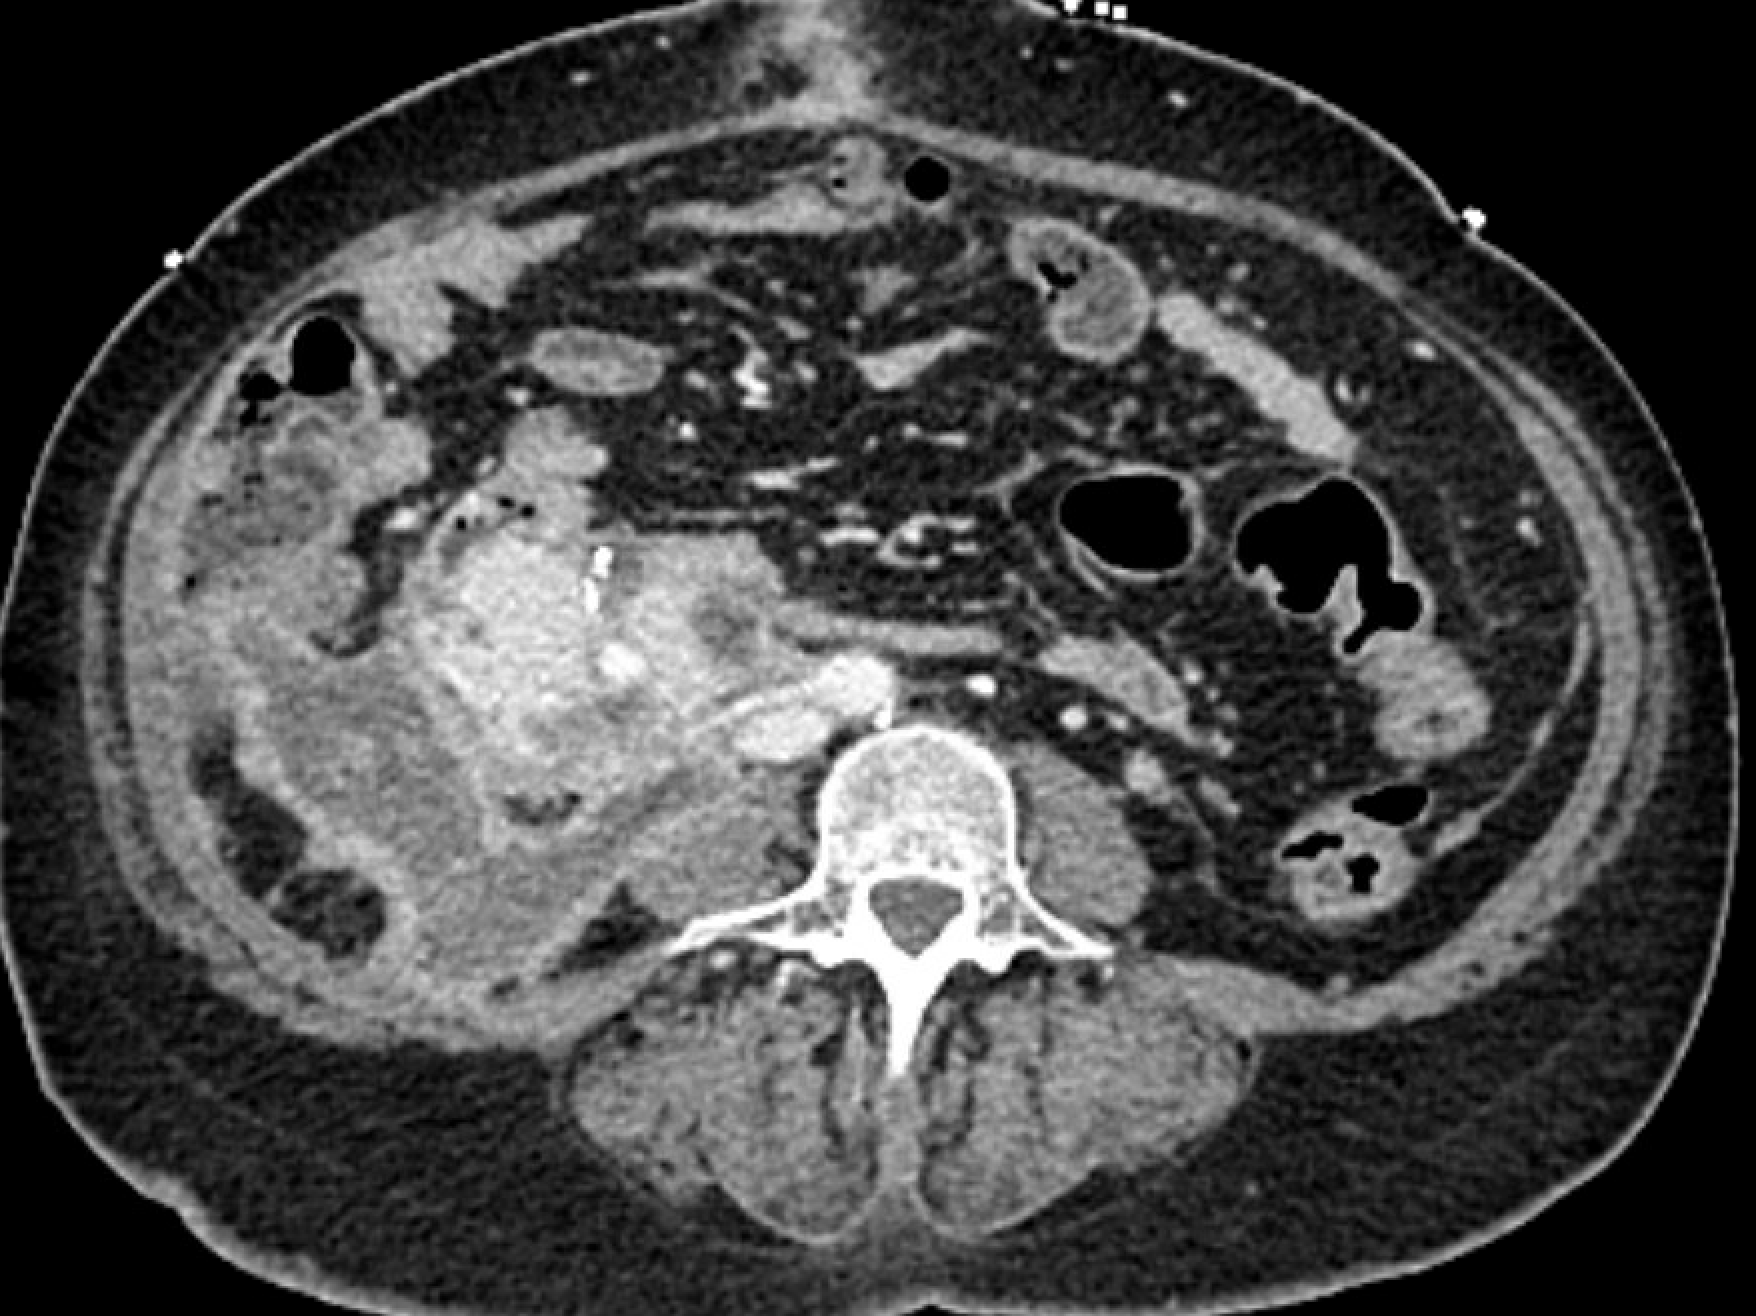

A 34 year old diabetic patient with end stage renal failure underwent combined pancreas-kidney transplantation and had early graft pancreatitis and delayed renal allograft function requiring laparotomy for bleeding after a kidney biopsy and two subsequent exploratory laparotomies for washout. She recovered good function of both pancreas and kidney but two months post-transplant developed a peri-pancreatic abscess as shown in the figure.